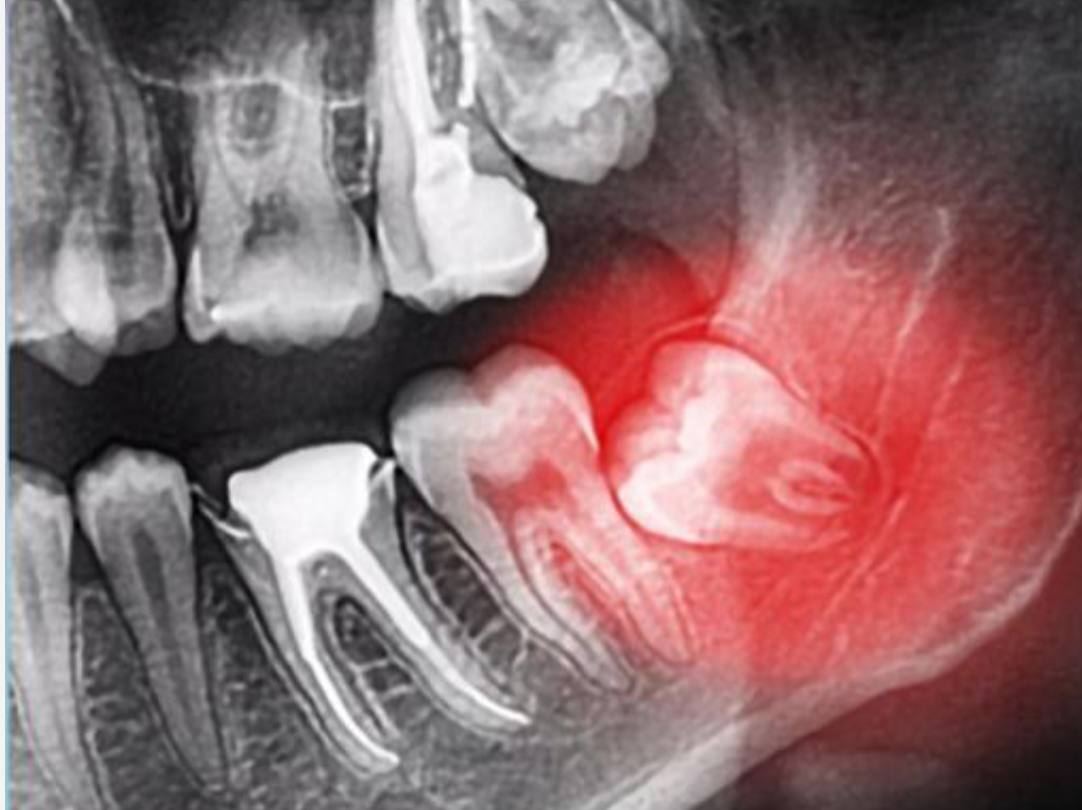

در واقع اگر دندان عقل شما مانند دندانهای دیگر رشد کرده باشد به روشهای متداول و عادی کشیده خواهد شد و نیازی به جراحی دندان عقل .نیست اما اگر دندان عقل به طور کامل از لثه خارج نشود و مقداری از آن در ا لته بماند، نیاز به جراحی دارد که به این دندان دندان عقل نیمه نهفته میگویند جراحی دندان عقل نیمه نهفته توسط دندانپزشک انجام میشود و ضروری است که هر چه سریعتر دندان عقل نیمه نهفته جراحی شود زیرا میتواند سبب التهاب لثه و عفونت آن شود.